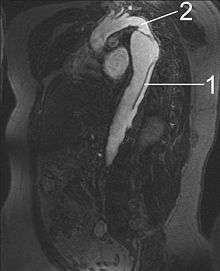

MRI

Magnetic resonance imaging (MRI) is currently the gold standard test for the detection and assessment of aortic dissection, with a sensitivity of 98% and a specificity of 98%. An MRI examination of the aorta produces a three-dimensional reconstruction of the aorta, allowing the physician to determine the location of the intimal tear and the involvement of branch vessels, and to locate any secondary tears. It is a noninvasive test, does not require the use of iodinated contrast material, and can detect and quantitate the degree of aortic insufficiency.

The disadvantage of the MRI scan in the face of aortic dissection is that it has limited availability and is often located only in larger hospitals, and the scan is relatively time-consuming, which may be dangerous in people who are already very unwell. Due to the high-intensity magnetic fields used during MRI, it is contraindicated in individuals with metallic implants. In addition, many individuals experience claustrophobia while in the MRI scanning tube.